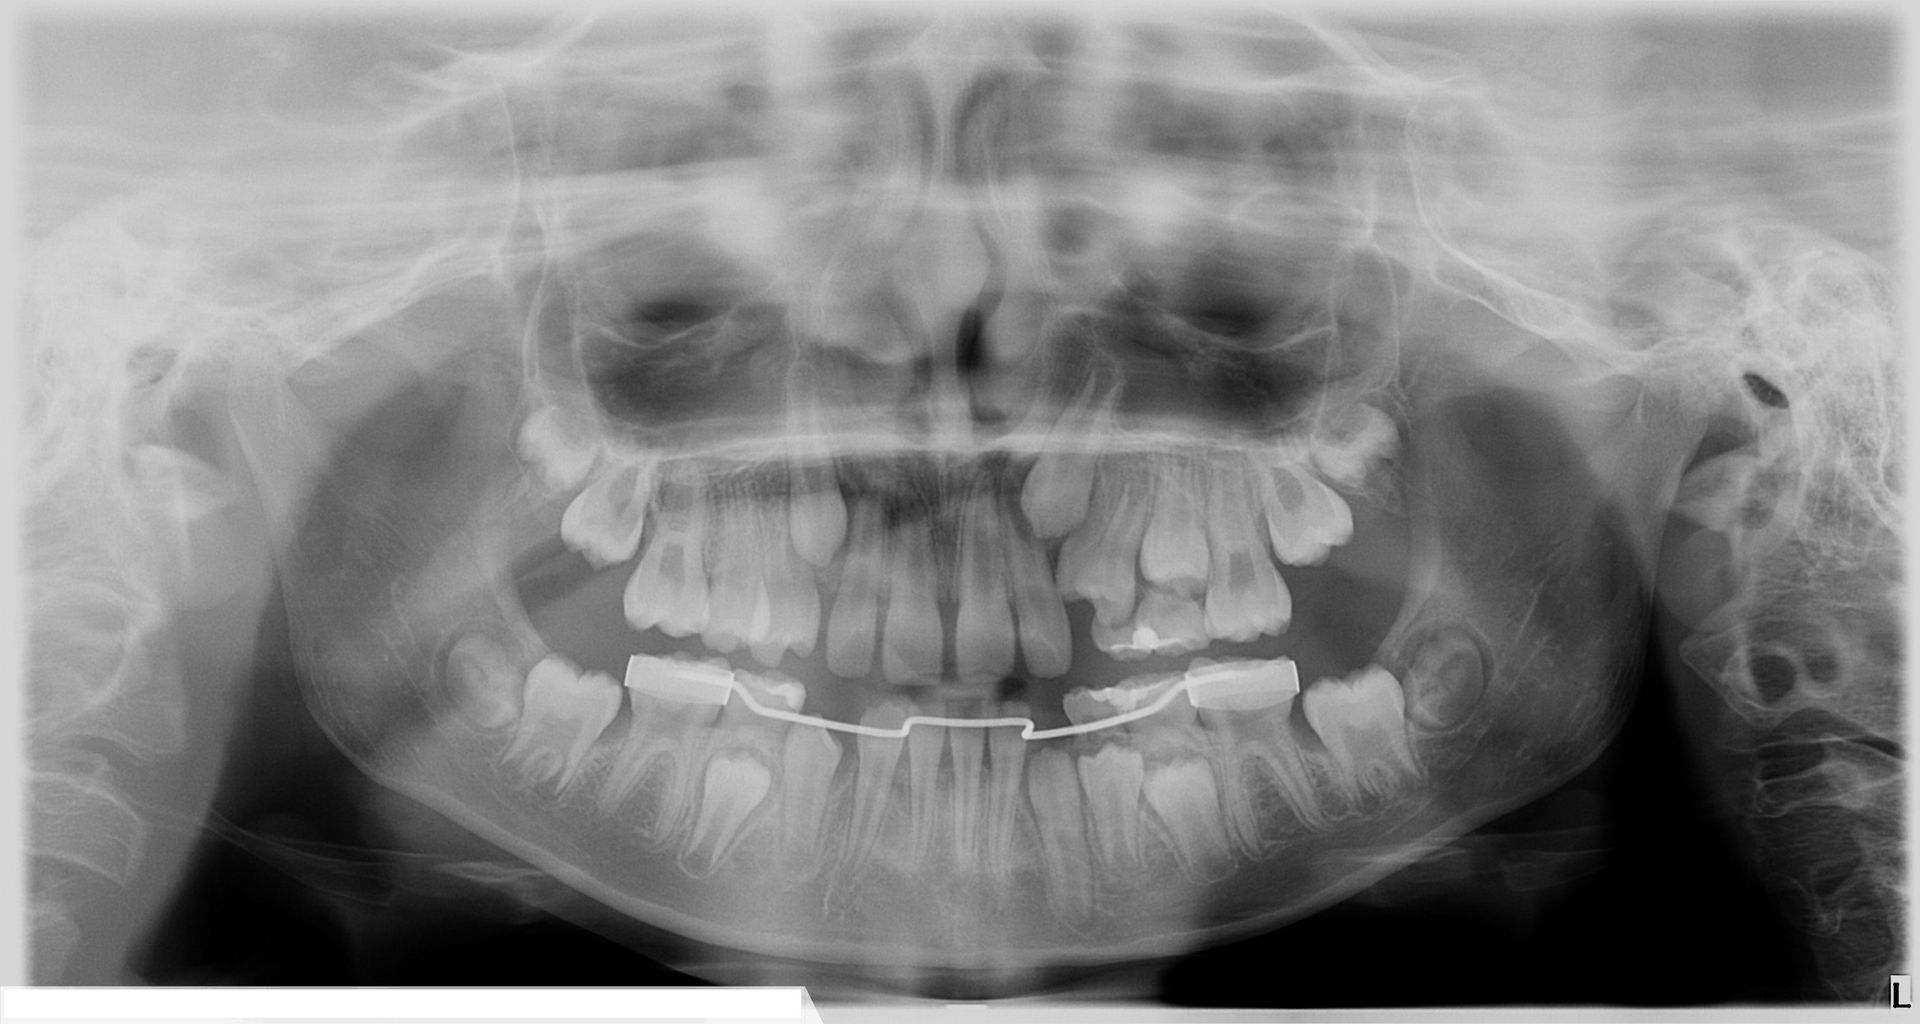

In this clinical case, a patient with impacted maxillary canines was re-evaluated using an i-CAT FLX from KaVo Imaging (manufactured by Imaging Sciences International LLC) The 3D views allowed for better determination of the clinical status of the patient by bringing more clarity to the labiolingual relationships of the impactions and the identification of any associated complications, such as root resorption in adjacent incisors.